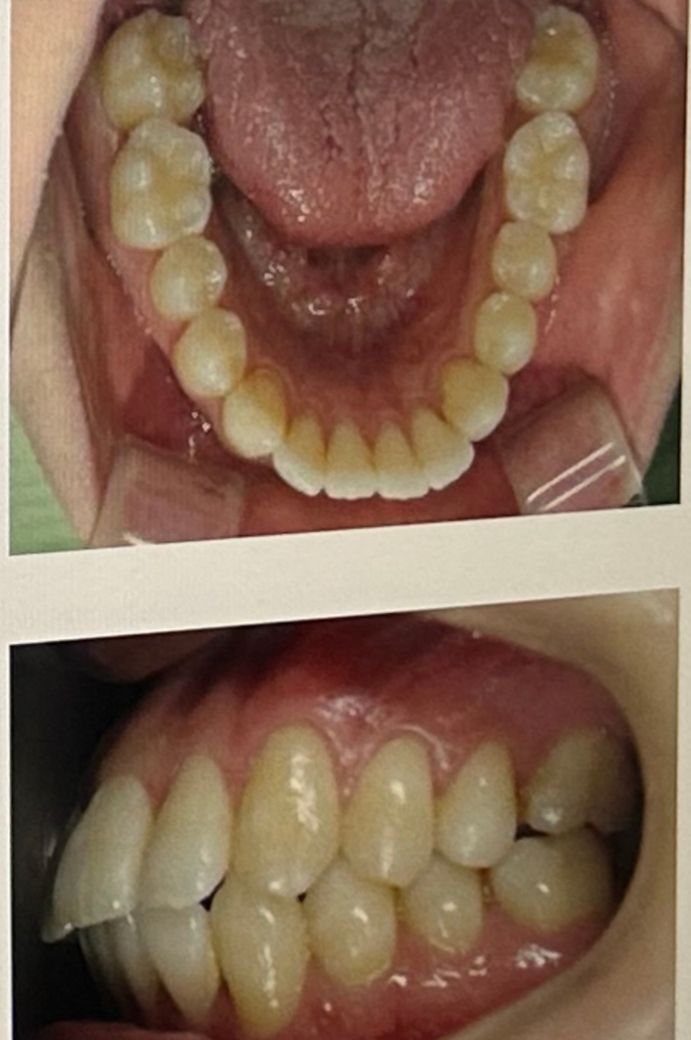

발치 교정이 필요한지 진단받고 싶어요

1. 돌출의 정도가 심한 편인지

2.외모적 관점말고 건강 관점에서 발치교정이 도움이 될지

어금니나 견치 교합은 상대적으로 안정된 상태인 반면, 앞니 돌출이 심한데 이런 경우 앞니를 집어넣기 위한 공간이 부족해 발치교정이 우선고려될 것 같습니다.